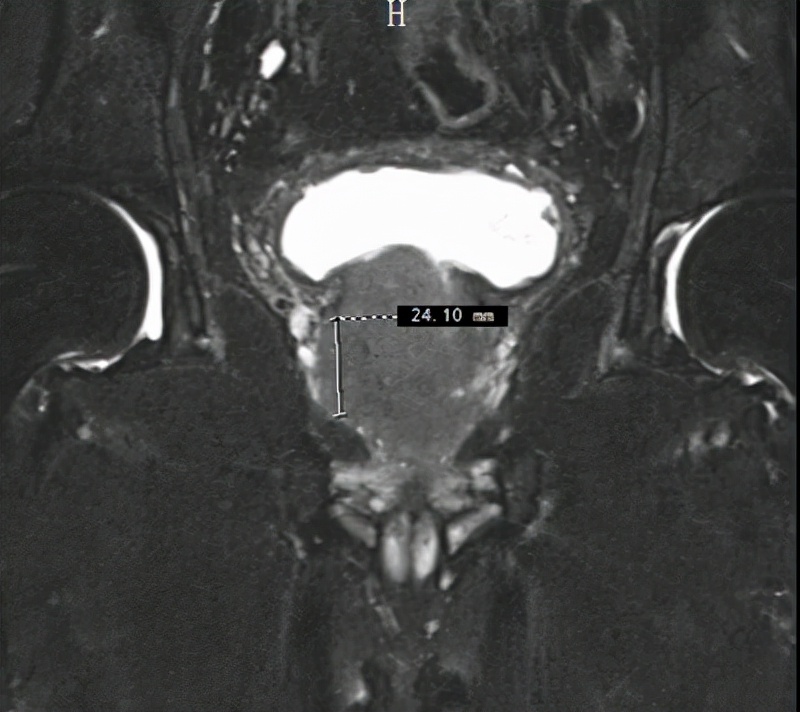

患者术前影像资料

据了解,任爷爷9月下旬到十堰人医做健康体检,经磁共振检查提示前列腺结节,同时前列腺总特异性抗原(TPSA)异常升高,10月3日收治于该院泌尿外科一病区,经进一步穿刺活检,确诊为高危前列腺癌。

十堰人医泌尿系统疾病中心常务副主任李云飞博士介绍,前列腺癌是中老年男性最为常见的恶性肿瘤之一,临床上对局限性前列腺癌分为低危、中危及高危三个层次,任爷爷的情况处于最高危,有扩散转移风险。同时任爷爷前列腺增生明显,严重影响到正常排尿,生活质量受到较大影响。